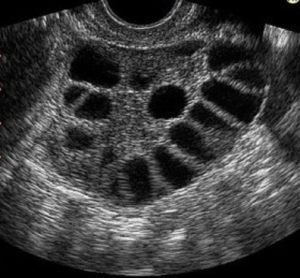

El síndrome de ovario poliquístico o SOP, es una enfermedad endócrina que afecta entre el 5%-10% de las mujeres en edad reproductiva y se caracteriza